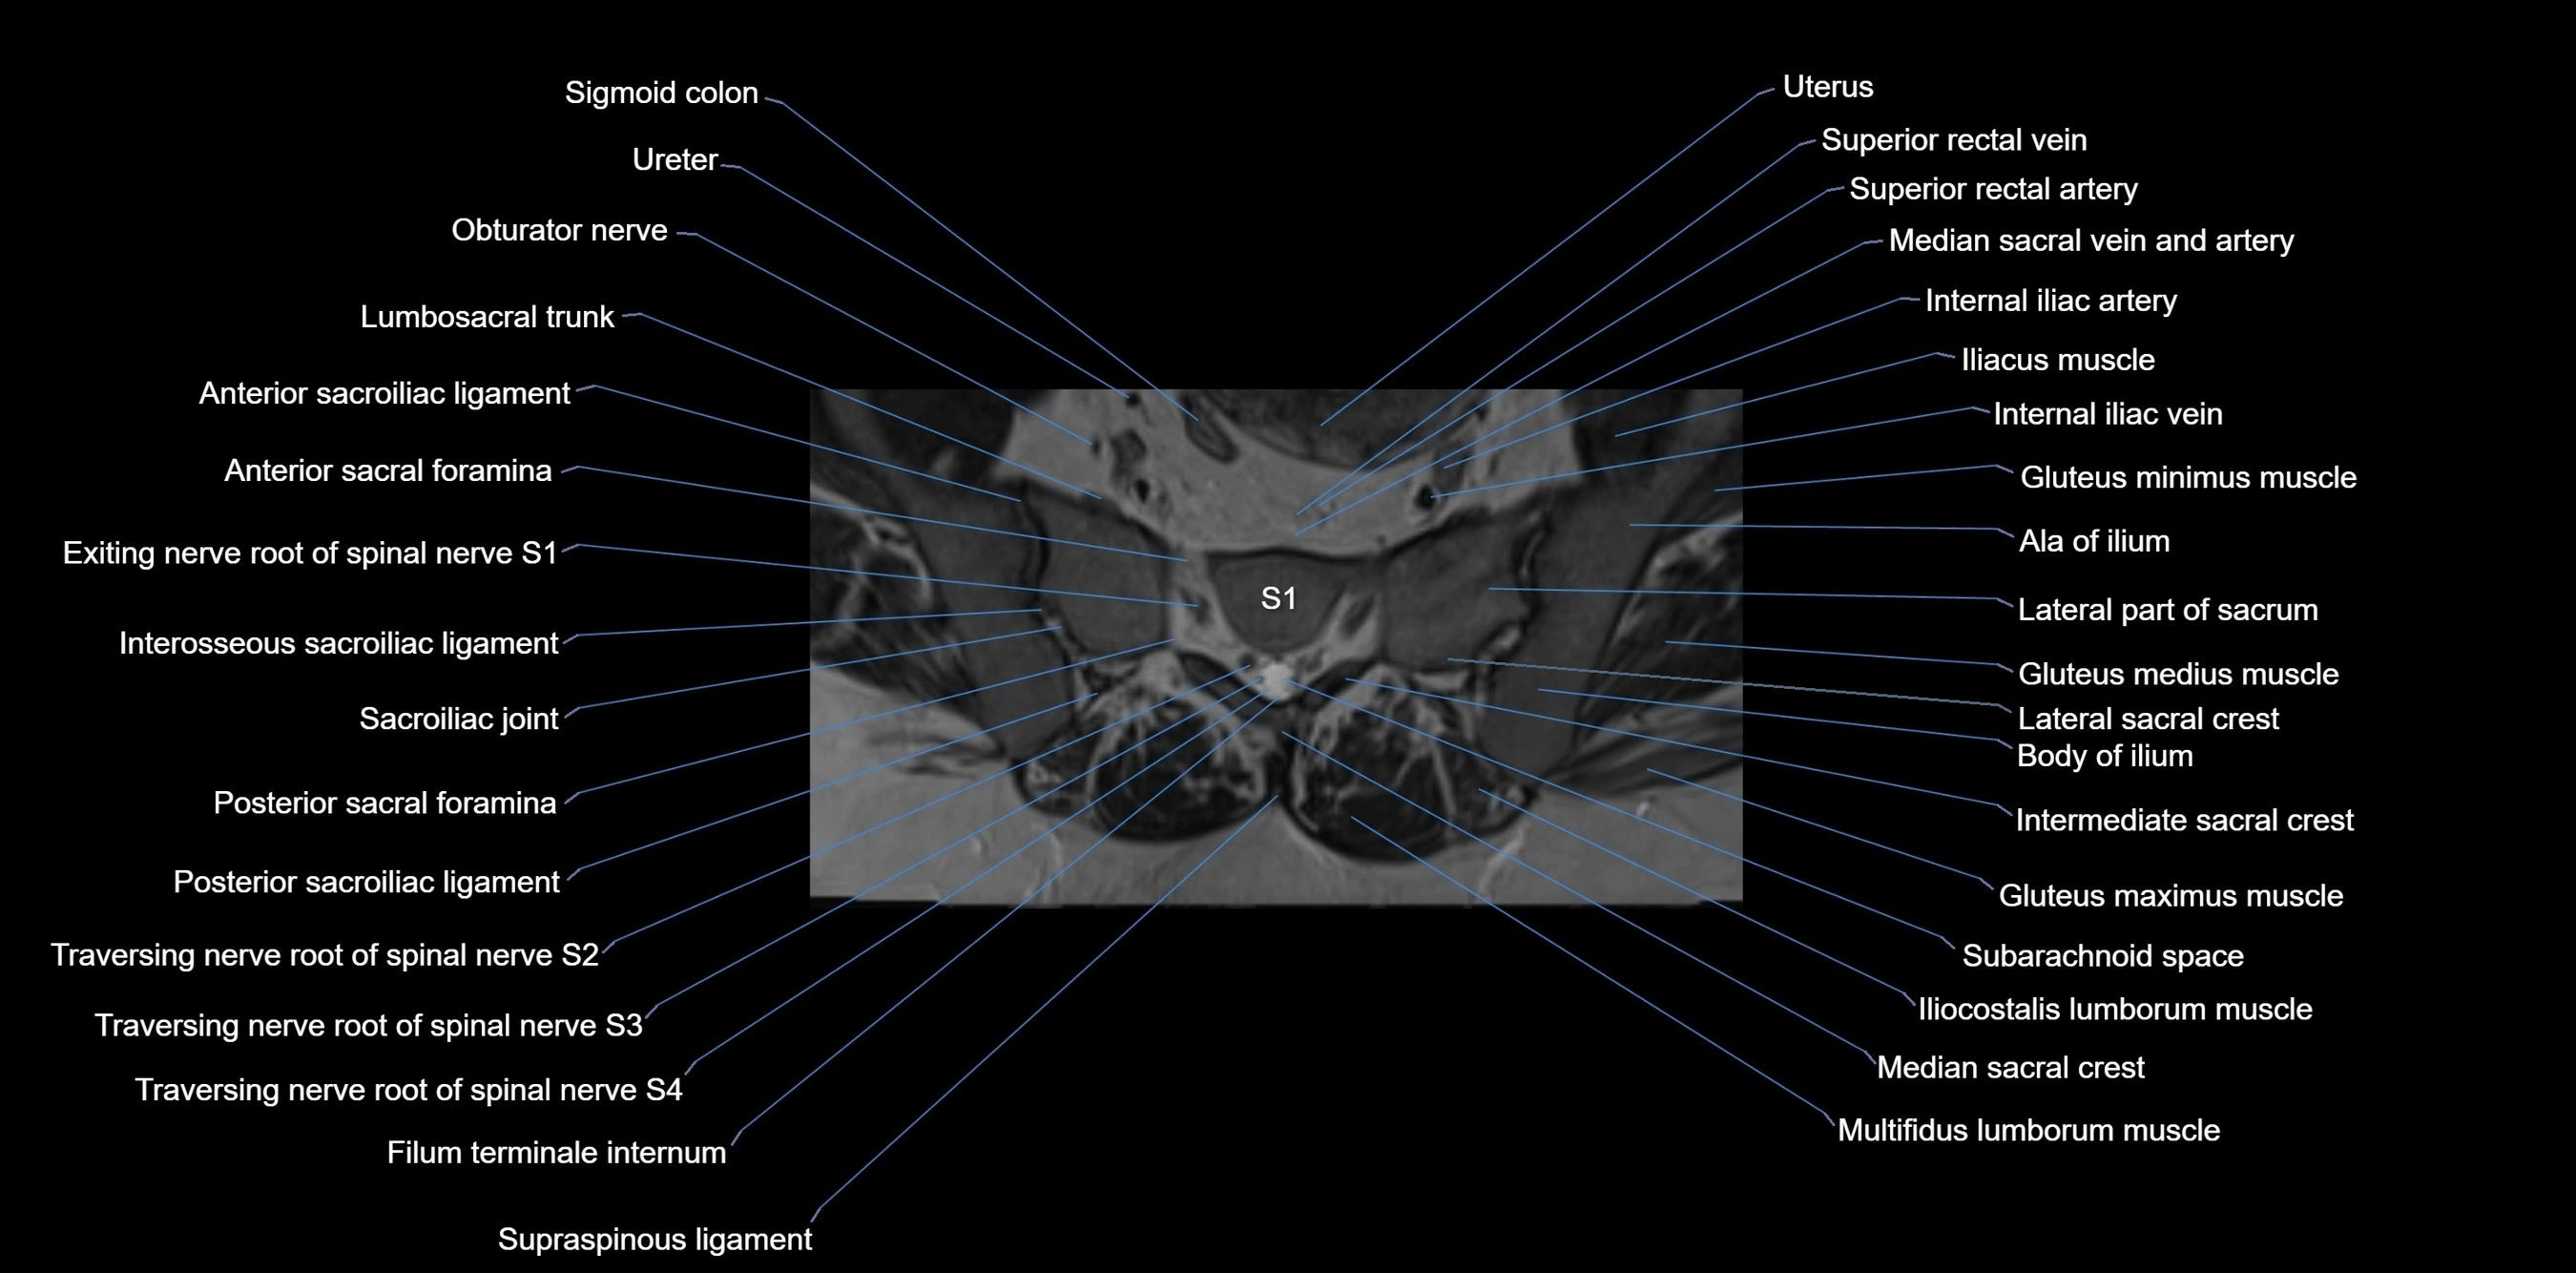

MRI image

image